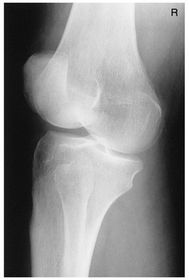

A. base of patella B. apex of patella C. tibial tuberosity D. neck of fibula E. head of fibula F. apex of head of fibula G. superimposed lateral and medial condyles H. patellar surface

Lateral Knee Mediolateral 40 SID 10x12 IR in table BUCKY - pt lateral recumbent w/ knee flexed 20-30 degrees so patella is perpendicular to IR - CR angled 5-7 degrees cephalic @ 1 in distal to medial epicondyle (Always angle for lateral) *seeing the adductor tubercle indicates the pt is underrotated* *seeing the distal borders of femoral condyles NOT superimposed indicates an incorrect cephalic CR angle*